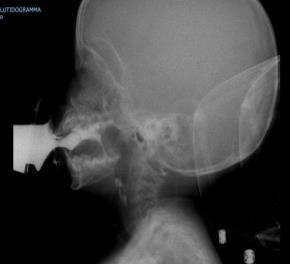

Videofluoroscopy

ORAL PREPARATORY PHASE IN EATING SOLID FOOD

✓ Loss of food out mouth, pushed out with tounge

✓ Food in anterior sulcus

✓ Limited tongue movement

✓ Problem about turning the food into bolus formation

✓ Food in valleculae and pharynx,

pre swallow

✓ Jaw grading inappropriate

ORAL PREPARATORY PHASE IN DRINKING LIQUID FOOD

✓ Loss of food out mouth

✓ Liquid in anterior sulcus

✓ Food pushed out with tounge

✓ Food in valleculae and pharynx, pre swallow

ORAL PROPULSIVE. PHASE:

✓ Food or liquid remains in anterior and/or lateral sulcus

✓ Food or liquid remains on floor of mouth

✓ Limited posterior tongue movement

✓ Reduced base of tongue action

✓ Tongue-soft palate contact incomplete

✓ Multiple swallows per bolus

✓ Delayed oral transit time

PHARYNGEAL PHASE

✓ Nasopharyngeal regurgitation

✓ Slow bolus passage through Pharynx

✓ Reduced pharyngeal contraction/motility

✓ Residue cleared with next swallow

✓ Residue not cleared

✓ Reduced hyolaryngeal execursion

✓ Penetration to underside of epiglottis

✓ Penetration to laryngeal vestibule

✓ Aspiration before, during and after swallow

✓ Aspiration respons: not effective cough, no cough – silent aspiration

ESOPHAGEAL PHASE

✓ Slow bolus passage through UES

✓ Residual on UES

✓ Cricopharyngeal dysfunction

✓ Slow bolus passage through esophagus